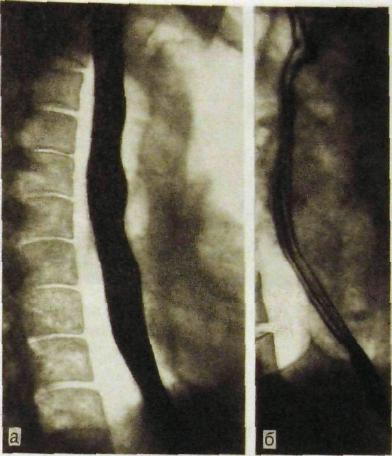

Современные технологии в медицине: рентгенодиагностика заболеваний желудка

Раздел: Фотогалерея мыслей